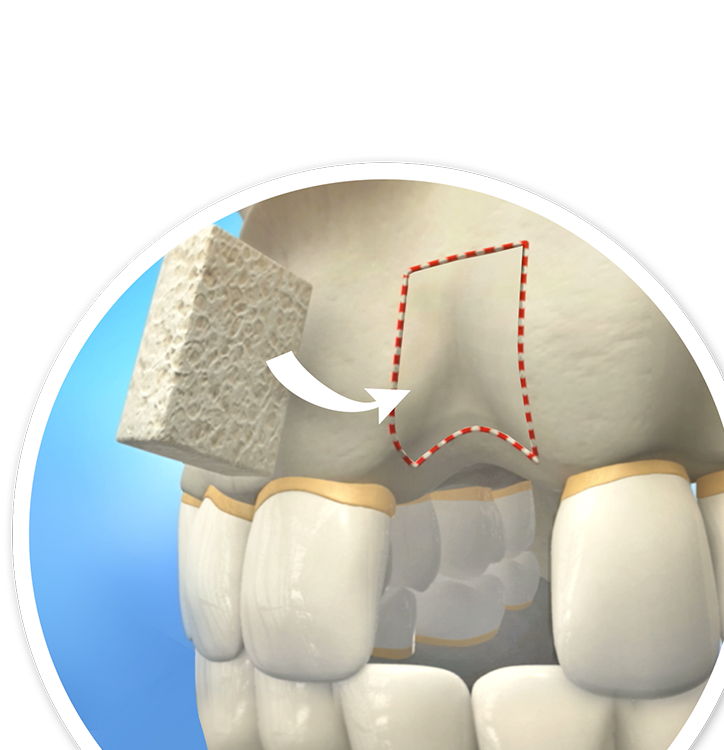

Bone Grafting

Facial trauma, unchecked gum disease, and tooth loss can result in jawbone recession, making it difficult to qualify for dental implants.

Bone grafting is a procedure designed to add volume and density to the jawbone and reestablish your candidacy for implant placement.

Bone grafting replaces deficient jawbone areas with healthy bone tissue, creating a stable foundation for your new dental implants.

The Bone Grafting Process

- Your dentist will conduct imaging to assess the quality and quantity of your bone tissue and decide where the bone grafts are needed.

- On the day of surgery, your dentist will create an incision in your gums and carefully place the synthetic grafting material or autologous bone tissue in the recessed jawbone.

- Your dentist will close the surgery site with sutures.